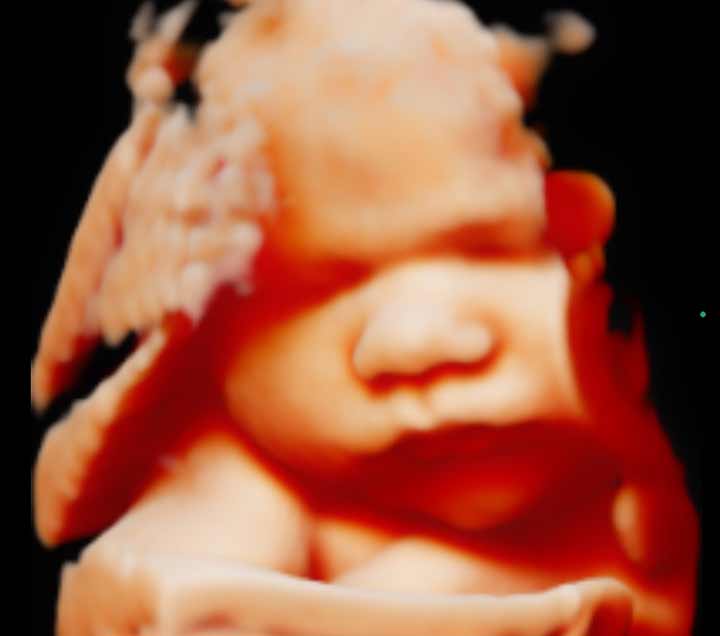

Samsung HERA 5D-s ultrahang eszközünk kiemelkedő lehetőség

genetikai vérvételre

(genetikai kombinált szűrés,(NIFTY, Trisomy, PrenaGenetics),

genetikai ultrahang vizsgálatokra, valamint az

5D-s babamozi is várja a kismamákat és családjaikat.